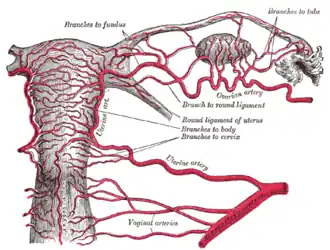

The arteries of the internal organs of generation of the female, seen from behind.

The arteries of the internal organs of generation of the female, seen from behind. -

In individuals who are biological females, the ovarian artery (a branch of the abdominal aorta) and uterine arteries form anastomoses.[6]

- the uterine arteries (from the anterior division of the internal iliac artery) and the ovarian arteries (from the aorta)